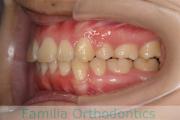

No.19V-044

- 主な症状:

- 上顎前突

- 年齢:

- 13歳

- 性別:

- 女性

- 抜歯部位

- 上:

- 44

- 下:

- 8558

- 主な使用装置:

- FEA

- 治療にかかった費用:

- 85万円

出っ歯を治したいということで小学生の時に来院されました。中学生になるまで経過観察をして、診断、上下左右から小臼歯を抜歯してマルチブラケット法にて治療を行いました。2年強、30回程度の通院が必要でした。

口元の突出感も大きく改善しています。

上下とも前歯の叢生(でこぼこ、凹凸、ガタガタ)がありましたので、保定をしっかりやらないと後戻りのリスクが出てきます。